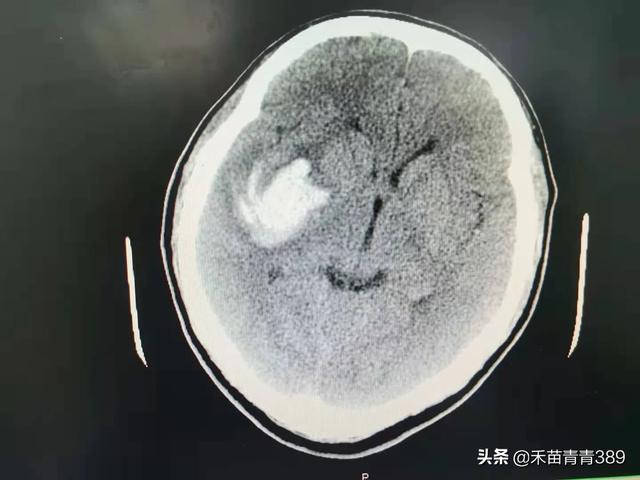

2022-09-22 01:43 阅读: 评论:脑出血是指原发性非外伤性脑实质出血,占急性脑血管病的20%~30%,约80%的出血部位发生在大脑半球,约20%的出血发生在脑干和小脑,发病年龄多在50岁以上,根据出血部位不同可分为,基底节区出血,丘脑出血,脑叶出血,脑干出血,小脑出血和脑室出血七种。根据病因不同,可分为原发性脑出血和继发性脑出血。根据出血量多少不同,临床症状轻重不同,严重者可昏迷,危及生命,一般脑出血症状表现有头疼,头晕,恶心,呕吐,言语不利,视物模糊,肢体活动障碍,意识改变,出现上述症状高度怀疑脑出血,尤其是平时血压高,和年龄大的患者,需要迅速到医院就诊,进行脑CT检查,当确诊脑出血后,立即住院治疗,住院后常规给予稳定血压,脑脱水降低颅内压和相关治疗。比较严重的脑出血是脑干出血,脑室出血,和出血量大患者,

死亡率比较高,大部分脑出血患者在内科药物保守治疗,出血量比较大的脑出血,脑室出血,需要外科开颅手术,或者颅穿引流,降低颅内压,防止脑疝形成。脑出血预后,与出血部位,出血量多少以及是否有合并症相关。一般急性期七天,两周后病情逐步稳定,经过积极治疗,绝大部分患者可以好转出院。脑出血康复和预防,要特别注意血压,控制血压在正常水平,要戒烟戒酒,清淡饮食,避免劳累,控制体重,规律休息,适当运动,稳定血糖血脂。